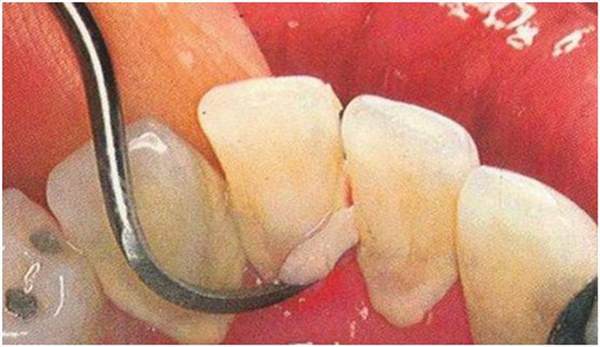

雖然目前還沒有一種方法可以阻止牙結石的形成,但可以通過機械的方法定期去除已形成的牙結石,也就是我們通常所說的潔牙或洗牙。這也是治療或預防牙齦出血的常用而基本的方法。洗牙的基本原理是通過機械的方法去除沉積在牙齒表面的結石,常見的有手工器械法和超聲波振動法兩種,而目前后者由于效率高、易掌握而使用更為普遍,洗牙的過程中會出現一些不適的感覺。如超聲波對某些人可能會刺激產生敏感的反應。這是正常現象,不過因此而對洗牙過于恐懼。由于結石的形成是目前尚無法阻止的,因而潔牙除了作為牙齦炎、牙周炎的治療措施外也是口腔健康維護的措施之一,需要定期進行,一般成人每年潔牙一次即可。

由于結石生長速度的個體差異較大,所以可根據個人情況酌情增減。